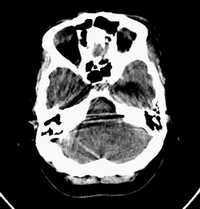

患者,女性,33岁,外伤检查发现,既往没有明显类似病史。

ct平扫见左侧脑室后角不规则形,边界不清的等密度肿块,肿瘤内有钙化,瘤周可见残存的脑室(低密度脑脊液影),考虑脉络脉丛乳头状瘤或室管膜瘤.

左侧侧脑室三角区占位性病变,其特点是平扫边界清、密度高、其内可见大块结节样的钙化,首先考虑起源于侧脑室三角区残余蛛网膜上皮的脑膜瘤可能性最大,无论是形态、密度、好发部位均符合脑膜瘤特点,建议增强进一步检查。

左侧脑室内软组织肿物,内部见多发不规则钙化,边界清楚锐利,有分叶。相应左侧脑室扩张。常见的不外乎3种病:室管膜瘤,脑膜瘤,脉络脉丛乳头状瘤。脑膜瘤分叶较少见,脉络脉丛乳头状瘤钙化较少见,因此,室管膜瘤可能性最大。

左侧脑室内见不规则略高密度团块影,边缘分叶,内见多发不规则钙化,病灶与侧脑室壁关系较为密切,左侧脑室扩大。考虑室管膜瘤可能性较大,其次为脑膜瘤,脉络丛乳头状瘤的可能性最小。